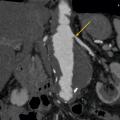

L’échographie-Doppler, l’angio-tomodensitométrie (angio-TDM [fig. 2] et l’angio-imagerie par résonance magnétique (angio-IRM) [fig. 3] permettent le diagnostic de sténose de l'artère rénale. Ils estiment à la fois le degré de sténose (exprimé en pourcentage de réduction du diamètre) et l’impact sur la vascularisation d’aval. Ces 3 examens sont validés et recommandés en première intention. Leur utilisation dépend de l’accessibilité et des habitudes locales. Il est à noter que l’écho-Doppler, très sensible et spécifique dans la sténose de l'artère rénale athéromateuse sous réserve d’un opérateur entraîné, est de sensibilité imparfaite dans la fibrodysplasie, dans laquelle l’angio-TDM est l’examen de référence.

Le tableau résume les avantages et inconvénients respectifs des 3 examens de référence. L’artériographie est réservée aux revascularisations (fig. 4), et n’a pas de place à titre diagnostique.

Dans la sténose de l'artère rénale athéromateuse, on retrouve une plaque habituellement unique, plus une moins calcifiée, ostiale, proximale ou tronculaire, responsable d’une réduction du diamètre endoluminal d’une ou des artères rénales (fig. 2 et 3).